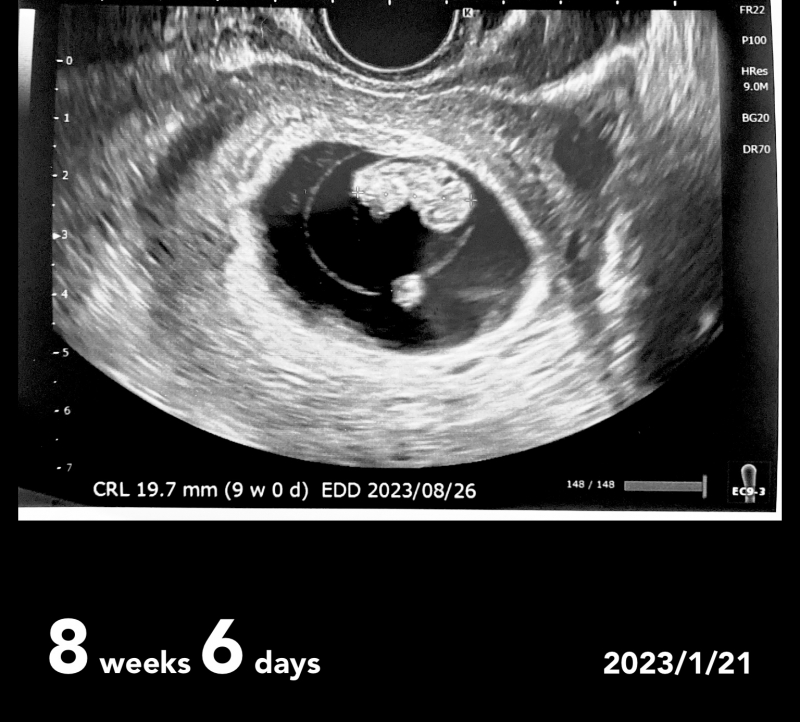

先週受診した時に頂いた8w6dのエコーを見てふと不安になったのですが、あかちゃんの背中に黒いスペースがあり、むくみがあるように見えます。

検診の時には先生から何も指摘はありませんでしたが、これはむくみでしょうか…

お腹の赤ちゃんお首のむくみについてですね。

赤ちゃんの首の後ろのところには、むくみがあることは多いと思います。

むくみがあったり、その程度によって必ず何かがあるというわけではありませんよ。

そしてむくみの大きさをみるのは10~14週ごろにみていくことを推奨されていることもあります。ご心配だと思うのですが、次回の健診の際に確認をされてみてはいかがでしょうか?